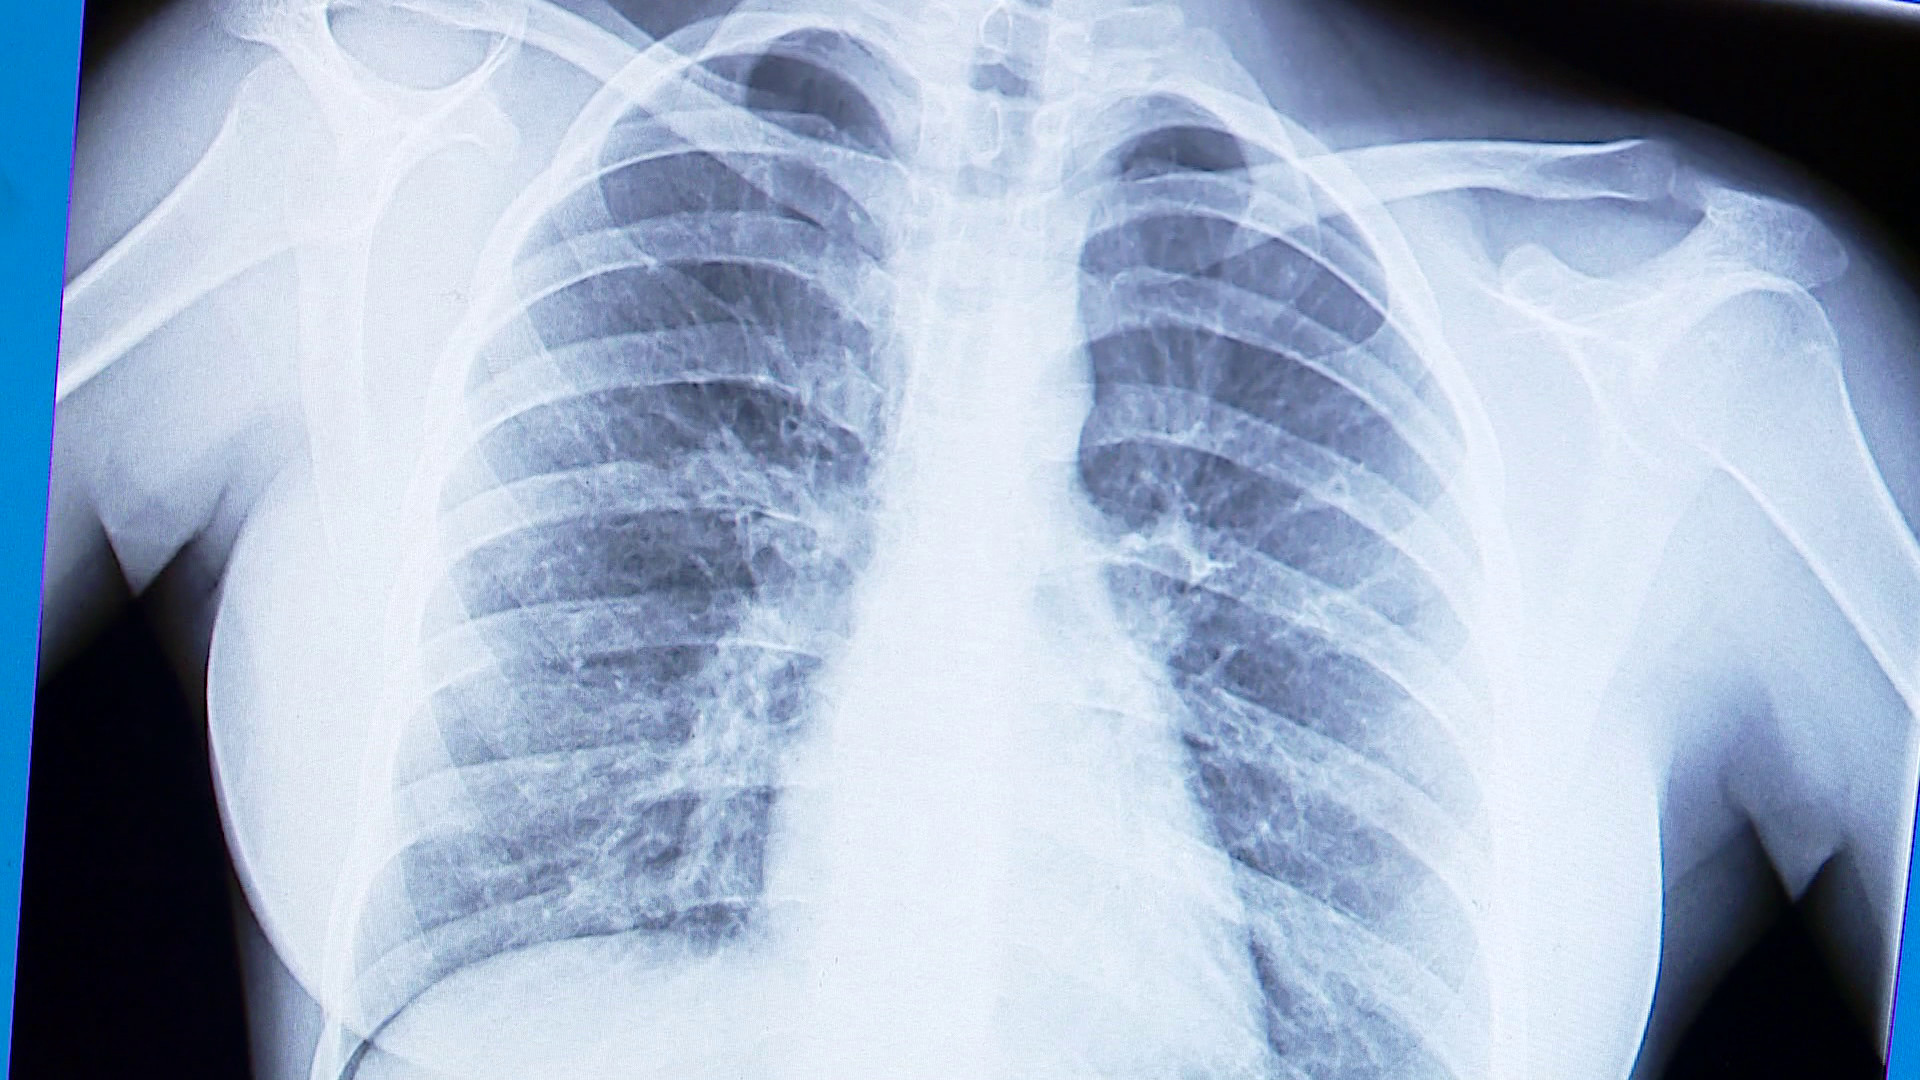

Być może potwierdzeniem tezy o szkodliwości e-papierosów jest przykład 16-latki, która niedawno trafiła na Oddział Pediatrii wejherowskiego szpitala. Od roku regularnie vapowała. Zdaniem lekarzy jej płuca wyglądały jak u 80-latki. U pacjentki doszło do uszkodzenia tkanki płucnej. Lekarze uważają, że te zmiany mogą być nieodwracalne. Pacjentka zmaga się z męczącym kaszlem, ale skutki vapowania mogą być też tragiczne.

– Pacjentka trafiła do nas z objawami dużej duszności, w stanie średnio ciężkim – wspomina Justyna Kiepuszewska, zastępca ordynatora Oddziału Pediatrii Szpitala Specjalistycznego w Wejherowie. – Początkowo myśleliśmy, że to zwykła infekcja. Dziewczyna gorączkowała i miała kaszel. W Polsce zanotowano jak na razie dwa zgony, które przypuszczalnie mogą mieć związek z używaniem sztucznych papierosów – dodaje.